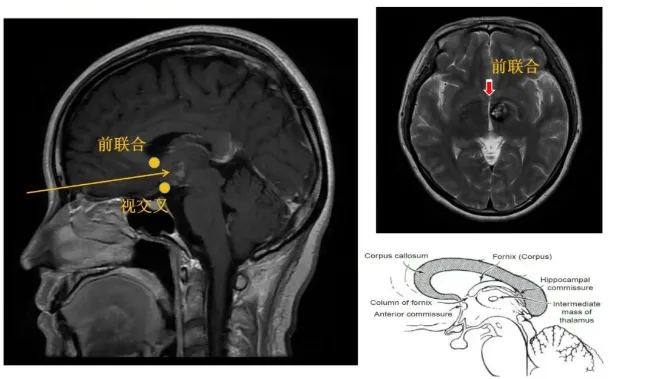

什么是丘脑?丘脑又称背侧丘脑,是间脑中较大的卵圆形灰质核团,位于三脑室两旁、由众多不同功能的神经核团组成,它是大部分传入性神经通路通向大脑皮质的换元站。丘脑位置深在、靠近功能区,有许多重要的神经核团,加上其本身及周围结构重要、复杂,丘脑位置的手术有肢体瘫痪、感觉障碍等风险大。